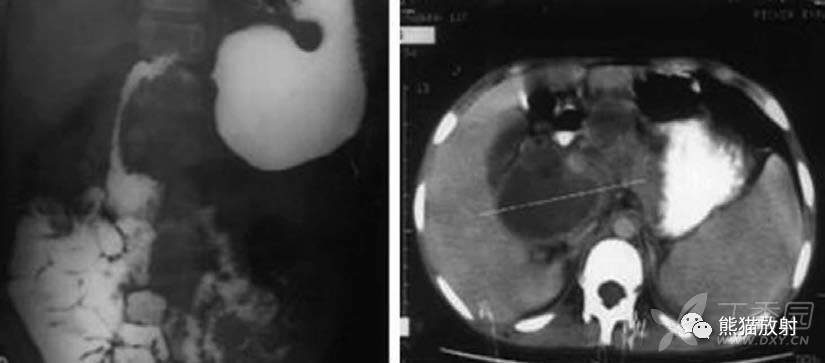

肝门区及腹膜后多发肿大淋巴结,部分融合,密度较低,环形强化。

中腹部小肠袢移位,MR冠状T1WI及T2WI可见肠系膜区多发增大淋巴结,其中心呈相对较低及较高信号。

吞钡可见食管狭窄伴溃疡和食管周围漏,CT显示食管壁环形厚伴食管周围漏,纵隔增大淋巴结。